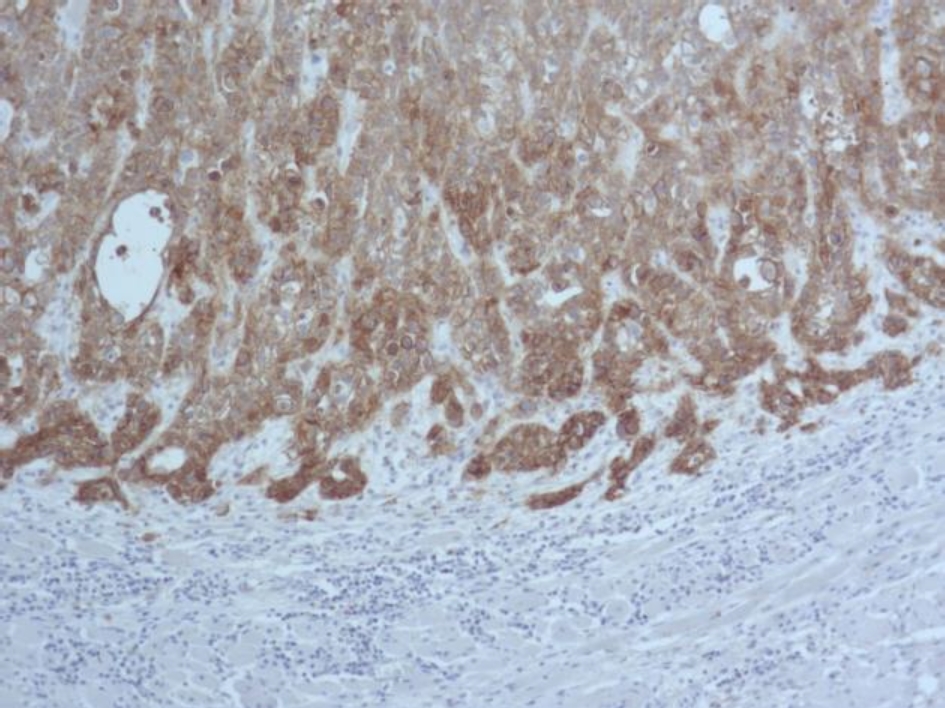

Во всех 19 исследуемых наблюдениях проведено дополнительное параллельное иммуногистохимическое исследование по выявлению экспрессии белков EGFR и Cyclin D1 соответственно, при этом диффузная, преимущественно умеренная экспрессия EGFR опреде-лялась в 17 (89 %) из 19 наблюдений (рис. 3), очаговая слабая экспрессия – в двух наблюдениях (11 %).

Экспрессия Cyclin D1 всех анализируемых наблюдений была очаговой, слабой и умеренной (рис. 4).

Рис. 3. Диффузная экспрессия EGFR в клетках плоскоклеточного рака языка. ИГХ окрашивание, ×100

Рис. 4. Очаговая слабая и умеренная экспрессия Cyclin D1 в клетках плоскоклеточного рака языка. ИГХ окрашивание, ×400

В нашем исследовании в 100 % наблюдений с амплификацией гена EGFR выявлена экспрессия белка EGFR, однако в 89 % экспрессия была сильной, а в 11 % наблюдений – умеренной. Исследователями также в 100 % наблюдений рака языка выявлено соответствие между амплификацией гена EGFR и экспрессией белка EGFR, однако наблюдения с высоким количеством копий EGFR сопровождались более интенсивной экспрессией белка EGFR при иммуногистохимическом исследовании. Мы не выявили такой закономерности.

Количество опухолевых клеток с амплификацией гена CCND1 в наших наблюдениях составило от 1 до 87, при этом гиперэкспрессии белка Cyclin D1 не определялось, экспрессия была очаговой, слабой и умеренной. По данным исследователей амплификация протоонкогена CCND1 при раке ротовой полости зависит от локализации, в частности, при раке языка составляет 88 [11] и 56,5 % [12], при плоскоклеточном раке щеки – 56 % [11], однако количество клеток с амплификацией не изучалось. В случаях разных категорий и степеней опухолевой дифференцировки определялась очаговая, слабая и умеренная экспрессия белка Cyclin D1, независимо от количества клеток с амплификацией протоонкогена CCND1. В работе исследователей также отсутствовала корреляционная связь между амплификацией CCND1 и экспрессией белка Cyclin D1 в случае плоскоклеточном раке полости рта [13].